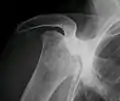

على الرغم أن المرض يمكن أن يؤثر على أي عظام، وأن نصف الحالات يظهر فيها تضرر مناطق متعددة، إلا أن النخر اللاوعائي يؤثر في المقام الأول على المفاصل في الكتف والركبة والأوراك.

النخر اللاوعائي يؤثر بشكل كبير على نهايات (كردوس أو منطقة النشأ العظمي) العظام الطويلة مثل عظمة الفخذ (عظمة تمتد من مفصل الركبة حتى مفصل الورك). من المواقع الأخرى الشائعة العضد (عظم الذراع العلوي)، [17][18] الركبتين، [19][20] الكتفين، [17][18] الكاحلين والفك.[21] المرض قد يصيب عظمة واحدة فقط، أو عظام متعددة في نفس الوقت، أو عظام مختلفة في أوقات مختلفة.[22] النخر اللاوعائي عادة يصيب الأشخاص في السن بين 30 و 50 سنة، ونخر رأس عظمة الفخذ يصيب ما بين 10.000 إلى 20.000 شخص سنويا في الولايات المتحدة. عندما يصيب المرض رأس عظمة الفخذ في الأطفال، يؤدي إلى ما هو معروف بمتلازمة ليج-كالفي-بيرث.[23]